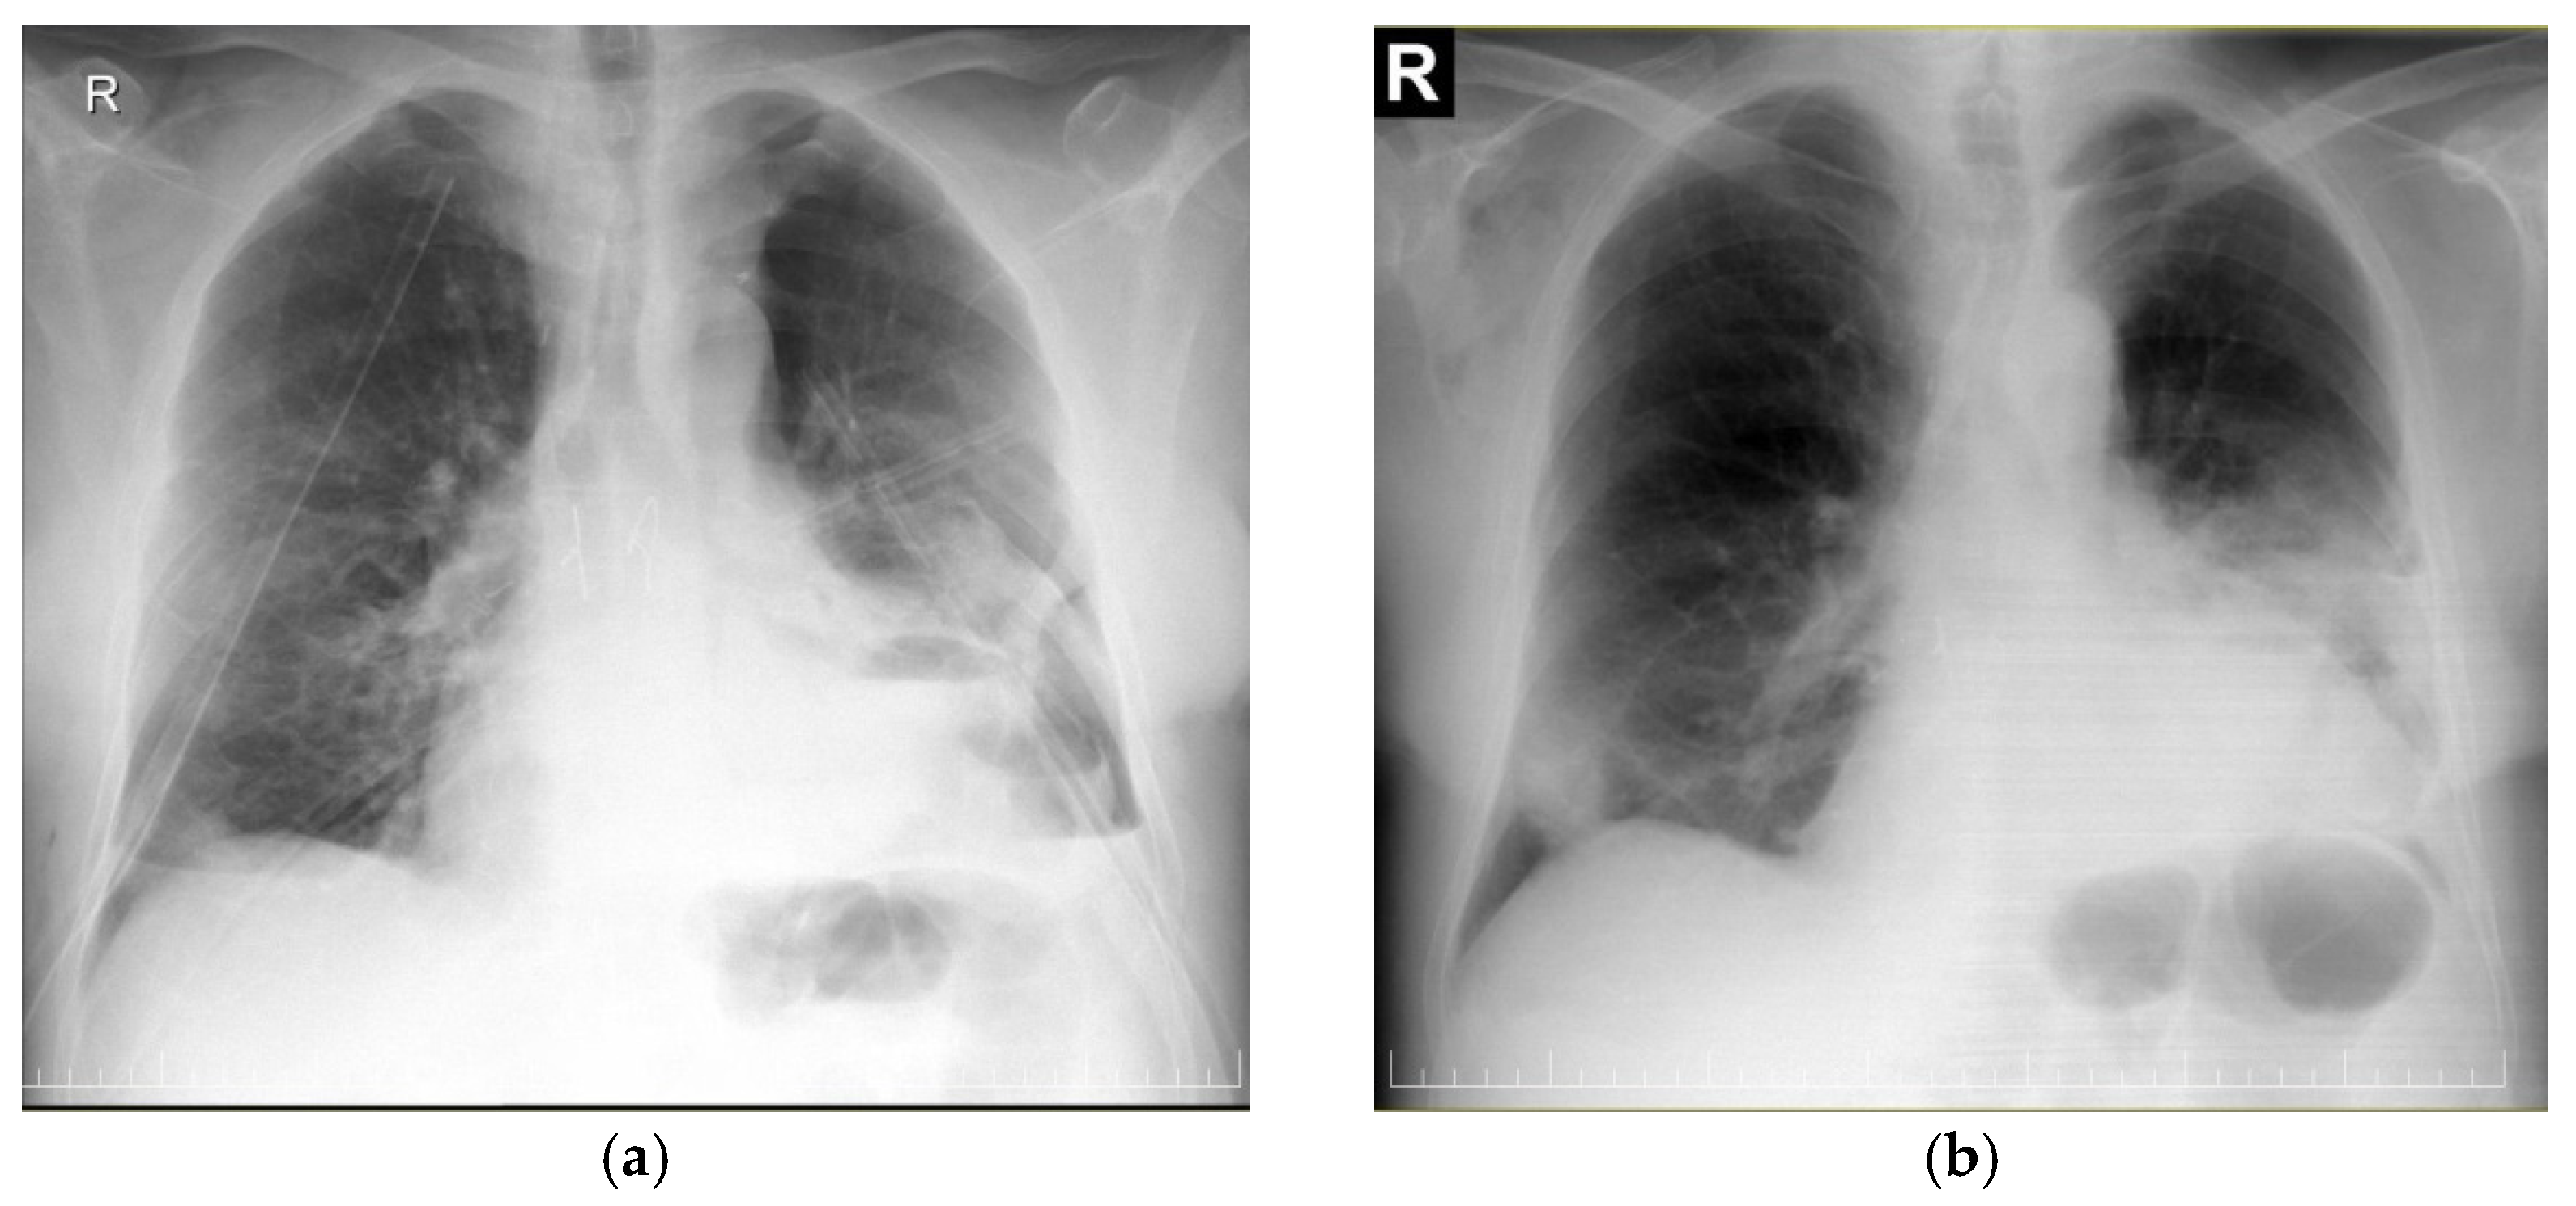

| CRC Stadium | Clinical-Radiological Findings |

| CRC 1 (minimal compression) |

|

| CRC 2 (moderate compression) |

| CRC 3 (“giant mediastinal tumor”) | |

| CRC 3A |

| CRC 3B |